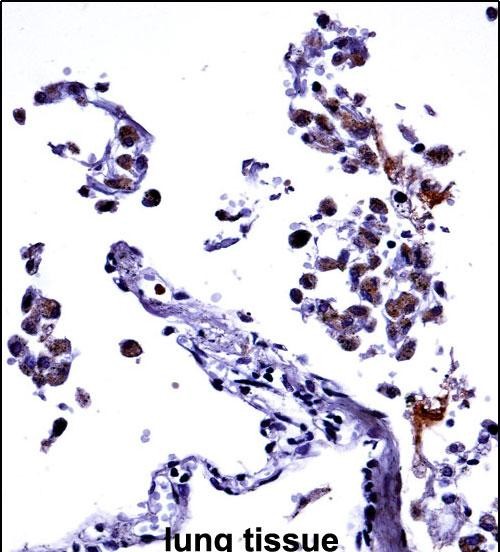

| IHC | 1/100-1/500 | Human,Mouse,Rat |